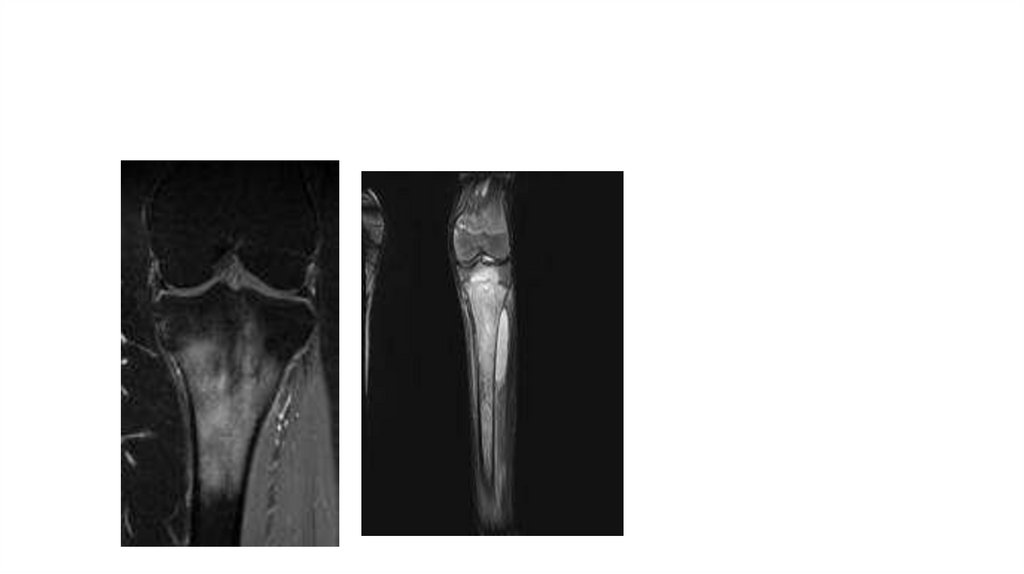

Воспалительные заболевания опорнодвигательного аппарата

«Воспалительные

заболевания опорнодвигательного аппарата»